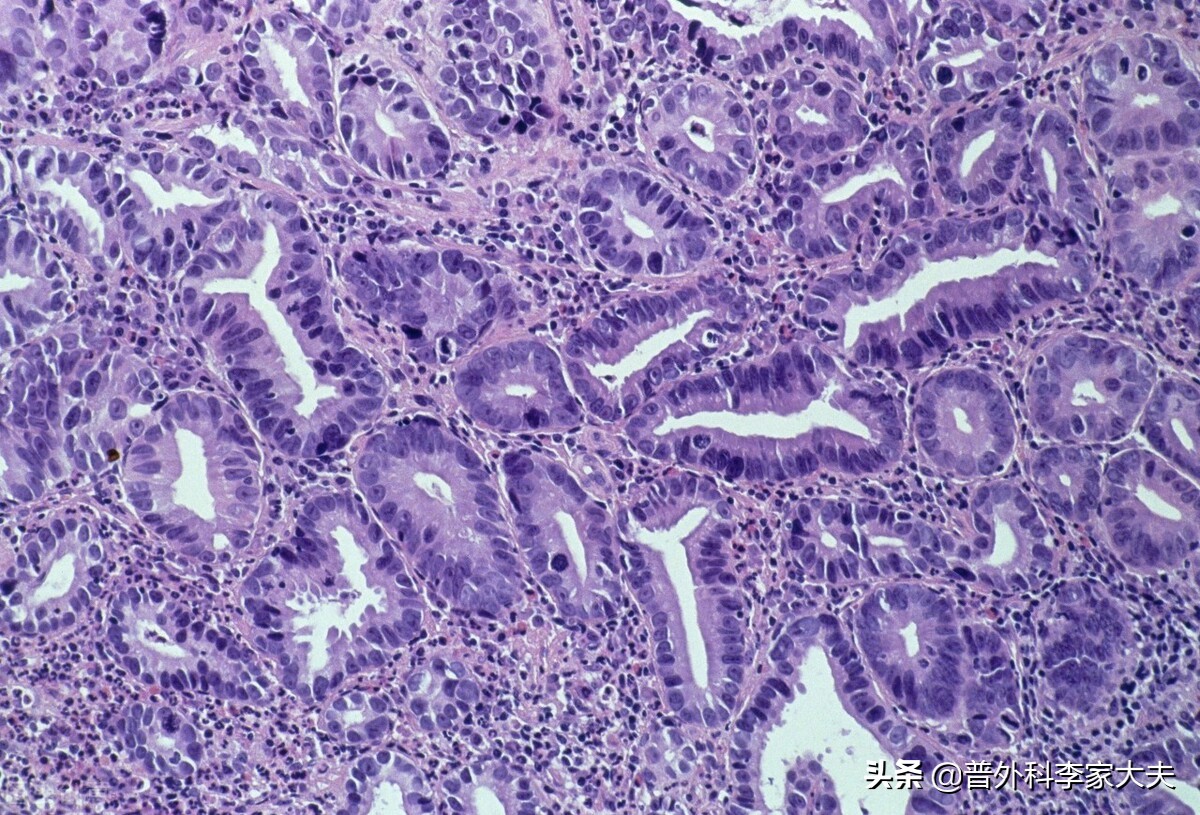

胃癌起病于粘膜层,但随着胃癌的进展,胃癌细胞就可能通过胃丰富的淋巴与血管网,进行由近向远的淋巴转移。以及伴随血液循环转移到肝、肺、腹膜、肾上腺、肾、脑、骨髓等远处脏器组织。当胃癌进展并突破胃的浆肌层后,胃癌细胞就容易发生种植转移与扩散转移了。由于胃肠本身的运动功能与胃处于宽阔腹腔内。因此,由胃脱落进入腹腔的癌细胞,就很容易扩散转移种植至壁层与脏层腹膜、腹与盆腔器官表面了,从而造成了胃癌广泛与复杂的转移。

胃癌细胞

因此,一旦某处胃细胞癌变,也意味着其他部位的胃粘膜细胞,也成为胃癌病变进程中的病变细胞之一。并且,随着原发胃癌的不断增殖进展,在这些致癌因素的继续影响下,部分原发癌细胞会发生癌基因的变异。与此同时,其他部位的胃病变细胞,也会进展成为新发的胃癌细胞。这些新发与基因变异后原发癌细胞,往往是在胃癌抗癌治疗中产生的,自然免疫逃逸能力得到了进一步加强,这也是为什么化疗药物效果好的胃癌患者,治疗过程中慢慢出现疗效差问题的原因。